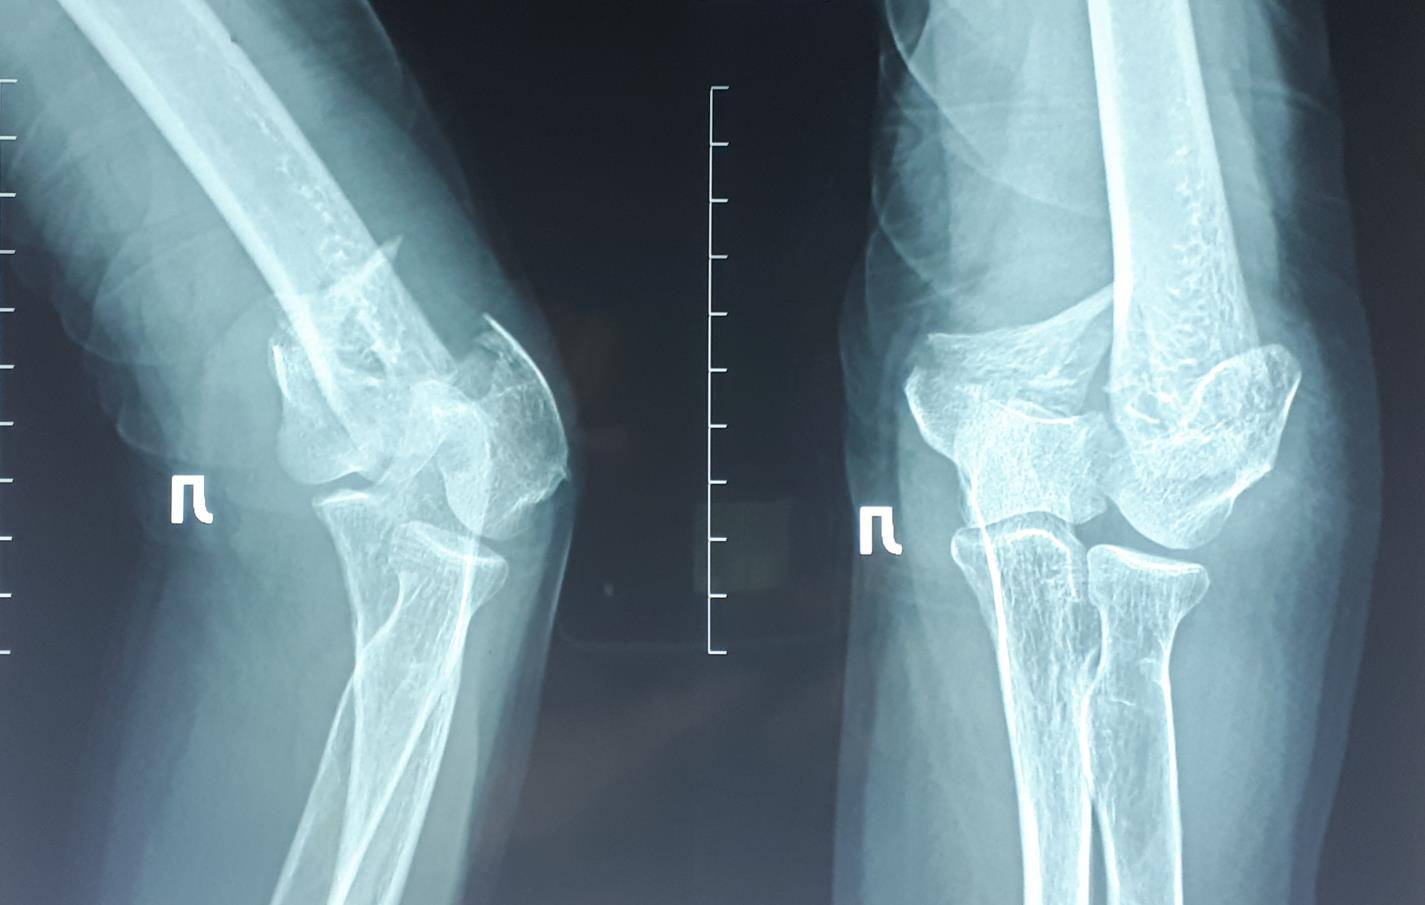

Перелом на уровне локтевого сустава. Перелом мыщелков плечевой кости.

Перелом локтевого сустава не медицинский термин, собственно говоря в суставе может произойти вывих, разрыв связок, а ломаются кости, образующие сустав, в случае локтевого сустава это нижний конец плечевой кости или верхние концы лучевой и локтевой кости.

В этой статье мы рассмотрим один из наиболее тяжёлых переломов данной анатомической области – перелом нижней трети плечевой кости, её мыщелков, участвующих в образовании локтевого сустава.

Переломы нижней трети плечевой кости участвующей в образовании локтевого сустава, или переломы мыщелков плечевой кости является тяжёлой травмой, требующей продуманного хирургического подхода и характеризующейся сложным реабилитационным периодом и часто не удовлетворительными результатами лечения.

Переломы дистального отдела плечевой кости крайне тяжёлые, часто распростряняются на суставную поверхность, состоят из большого количества мелких осколков. В подавляющем большинстве случаев они требуют хирургического лечения, в противном случае крайне высок риск несращения, образования ложного сустава, сращения в порочном положении, посттравматического артроза сустава, контрактуры локтевого сустава.

На представленных ниже рентгенограммах локтевого сустава определяется оскольчатый перелом мыщелков левого плеча с 4 большими фрагментами.